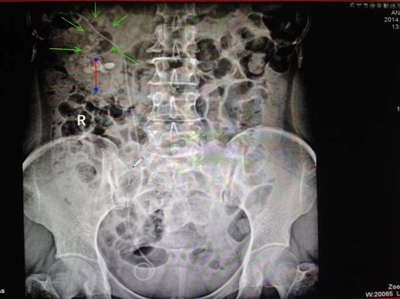

据了解,咸宁辛勤结石医院为患者吴女士成功施行输尿管软镜联合钬激光碎石取石术。术后患者自觉无创轻松,2小时即可正常活动,术后各项检查指标良好,B超、X线拍片显示,肾盂内3.5×2.2cm结石完全粉碎,短期内绝大部分碎砂排出体外,从手术到出院仅用5天时间。